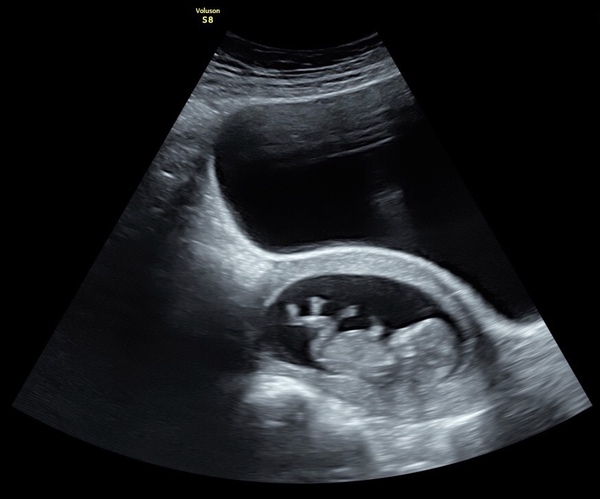

Hi all, my wife had a private scan yesterday which dated us even further ahead since our previous scan two weeks ago! According to them we are at 12 weeks as of yesterday. All appearing to be okay and we could see the little one kicking around energetically! Our NHS scan isn’t until 7th Jan, so will look to see if we can move it earlier as that could put us beyond the 14 week mark at that time. Hope all of you who are going for scans over the next few days hear the best of news and wish everyone a great Christmas and new year.

Let’s try this again... thanks @RedRobin7 for the heads up :)